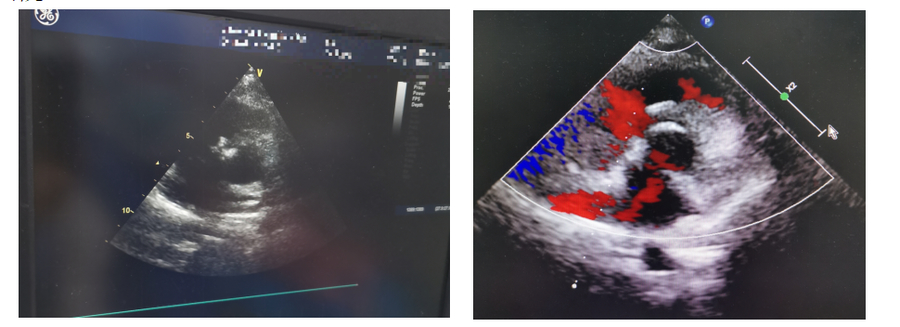

在过去的一段时间里,济南市儿童医院心血管内科李磊主任带领团队,凭借丰富的临床经验、精湛的介入技术和高度的责任心,成功为患儿实施了可降解封堵器植入手术。这些患儿年龄从2岁到9岁不等,术前经详细检查评估,均符合可降解封堵器治疗指征。手术在导管室进行,手术在超声引导下,医生通过股静脉或股动脉穿刺,将纤细的导管送达心脏缺损部位,精准释放可降解封堵器。整个手术过程创伤小、时间短,患儿术后恢复快,1周便顺利出院。

术后随访结果显示,接受可降解封堵器治疗的患儿心脏功能均恢复良好,室间隔缺损处无残余分流,生长发育状况得到明显改善,生活质量显著提高。患儿家长们对治疗效果非常满意,感谢医院为孩子们带来了健康和未来。